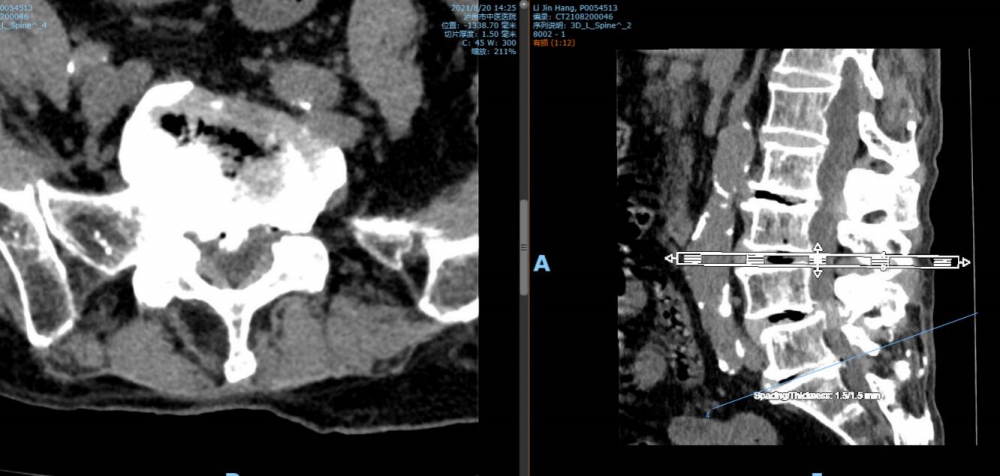

腰4 5椎間盤CT

腰5 骶1椎間盤CT

瀘州市中醫(yī)醫(yī)院骨傷二科主治中醫(yī)師胡建超介紹,李謹行老人患有腰椎管狹窄癥 、腰4椎I°滑脫 、脊柱退行性側(cè)彎畸形 、冠狀動脈粥樣硬化性心臟病、心律失常、高血壓2級等17種疾病,同時處于慢性阻塞性肺病加重期和腦梗塞恢復期。92歲、全身多種疾病,隨時可能會有突發(fā)情況,要做這樣一個大手術(shù),對醫(yī)生和患者來說,無疑都是一個巨大的挑戰(zhàn)。